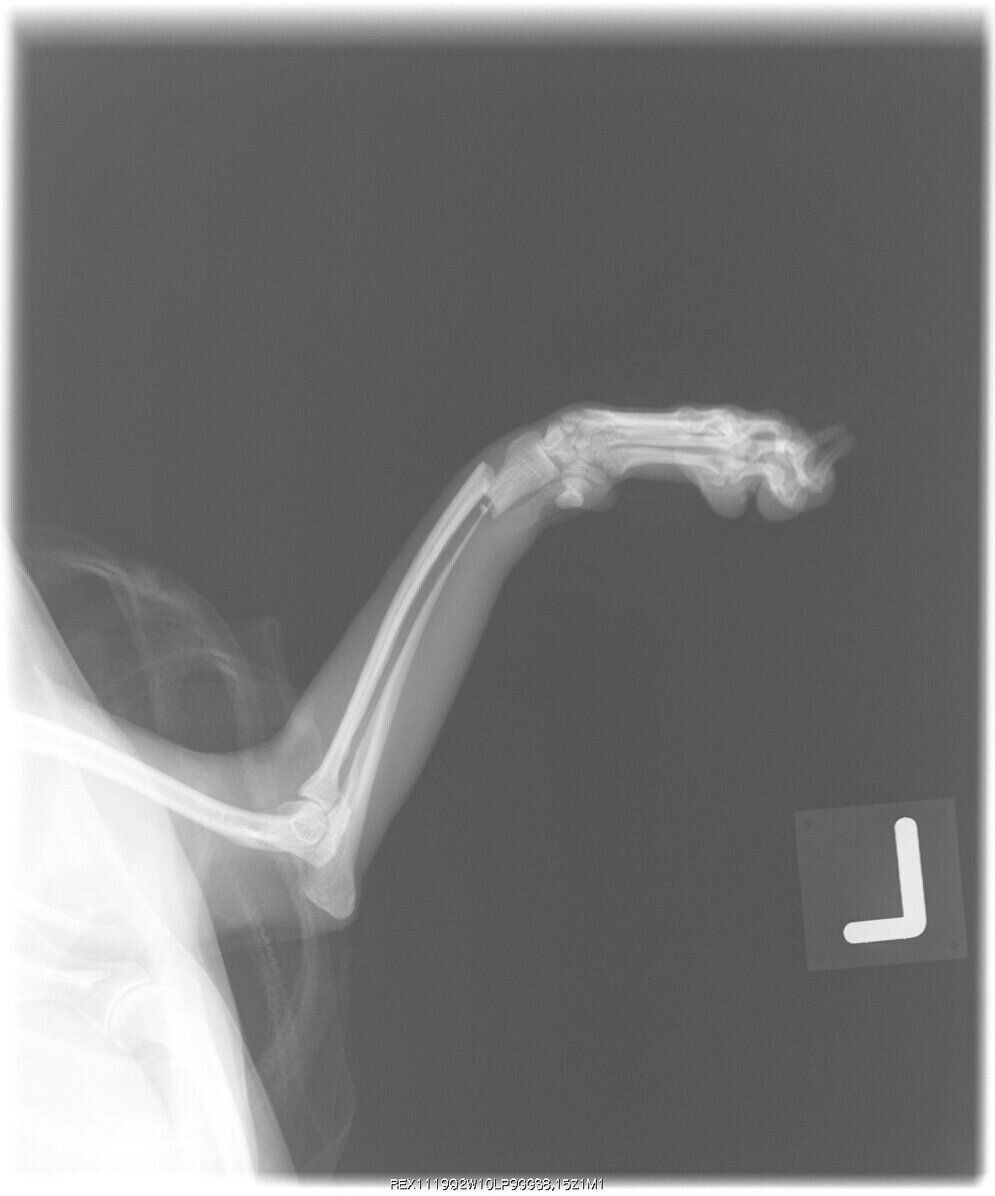

前足を骨折した、生後7カ月のトイ・プードルのエックス線写真

骨折は文字どおり、骨が折れてしまうことを指します。成長途中の犬は、ちょっとした衝撃で折れやすいです。犬の骨の成長は生後11カ月でいったん止まるといわれているので、それまでは強い衝撃を与えないように、とくに注意が必要でしょう。